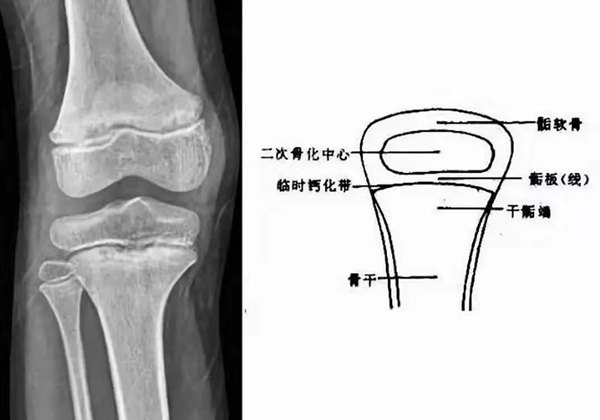

我們都知道,人體的高矮是由骨骼的生長發(fā)育決定的,特別是下肢長骨。長骨呈長管狀,在長骨的兩端有一種專管骨骼生長的骺軟骨,它與干骺端之間有一盤狀軟骨結(jié)構(gòu)稱為骺板(線),在幼兒的X光片上表現(xiàn)為一條較寬的透光帶。 (見下圖)

未成年時(shí)隨著年齡的增加骺軟骨端不斷骨化,骨骼就不斷增長。當(dāng)骨骺線完全閉合時(shí)骨骼就停止生長,個(gè)子也就不再增長了。一般骨骺端完全閉合的年齡是18~20歲左右。